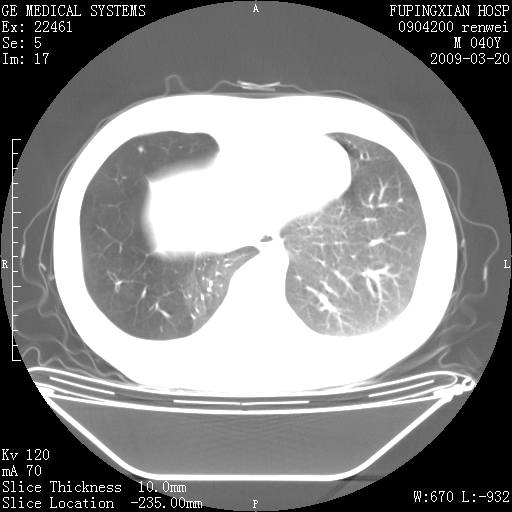

标题: CT18920:平时体健,体检时发现以下问题。

单侧肺气肿表现,原因?   特发性或先天性可能

右肺气肿。

右肺局限性肺气肿

右肺局限性肺气肿。

双肺弥漫磨玻样改变,肺纹理增重,考虑早期间质纤维化伴局部阻塞肺气肿,[考虑黏液栓]

右肺局限性肺气肿;[考虑黏液栓]所致。

透明肺

双肺弥漫磨玻样改变,右肺局限性肺气肿。病人没有症状?

考虑间质性肺炎伴右侧局限性肺气肿,

先天性支气管闭锁

右肺局限性肺气肿,原因?先天支气管闭锁?粘液栓?